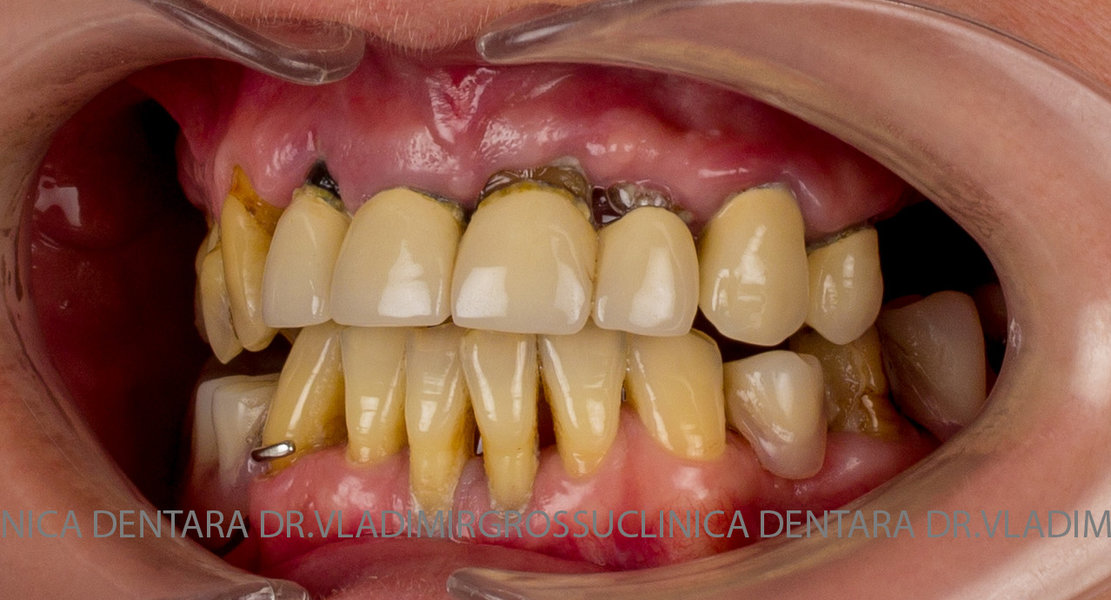

Cazuri clinice conceptul All-on-6

Caz 1